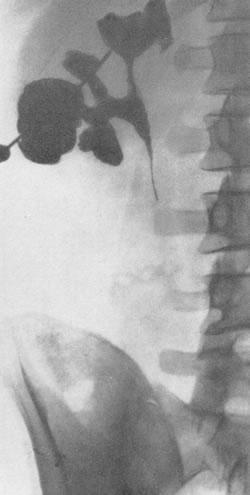

Понимание кавернозного туберкулеза почки

Раздел: Мудрость в деталях